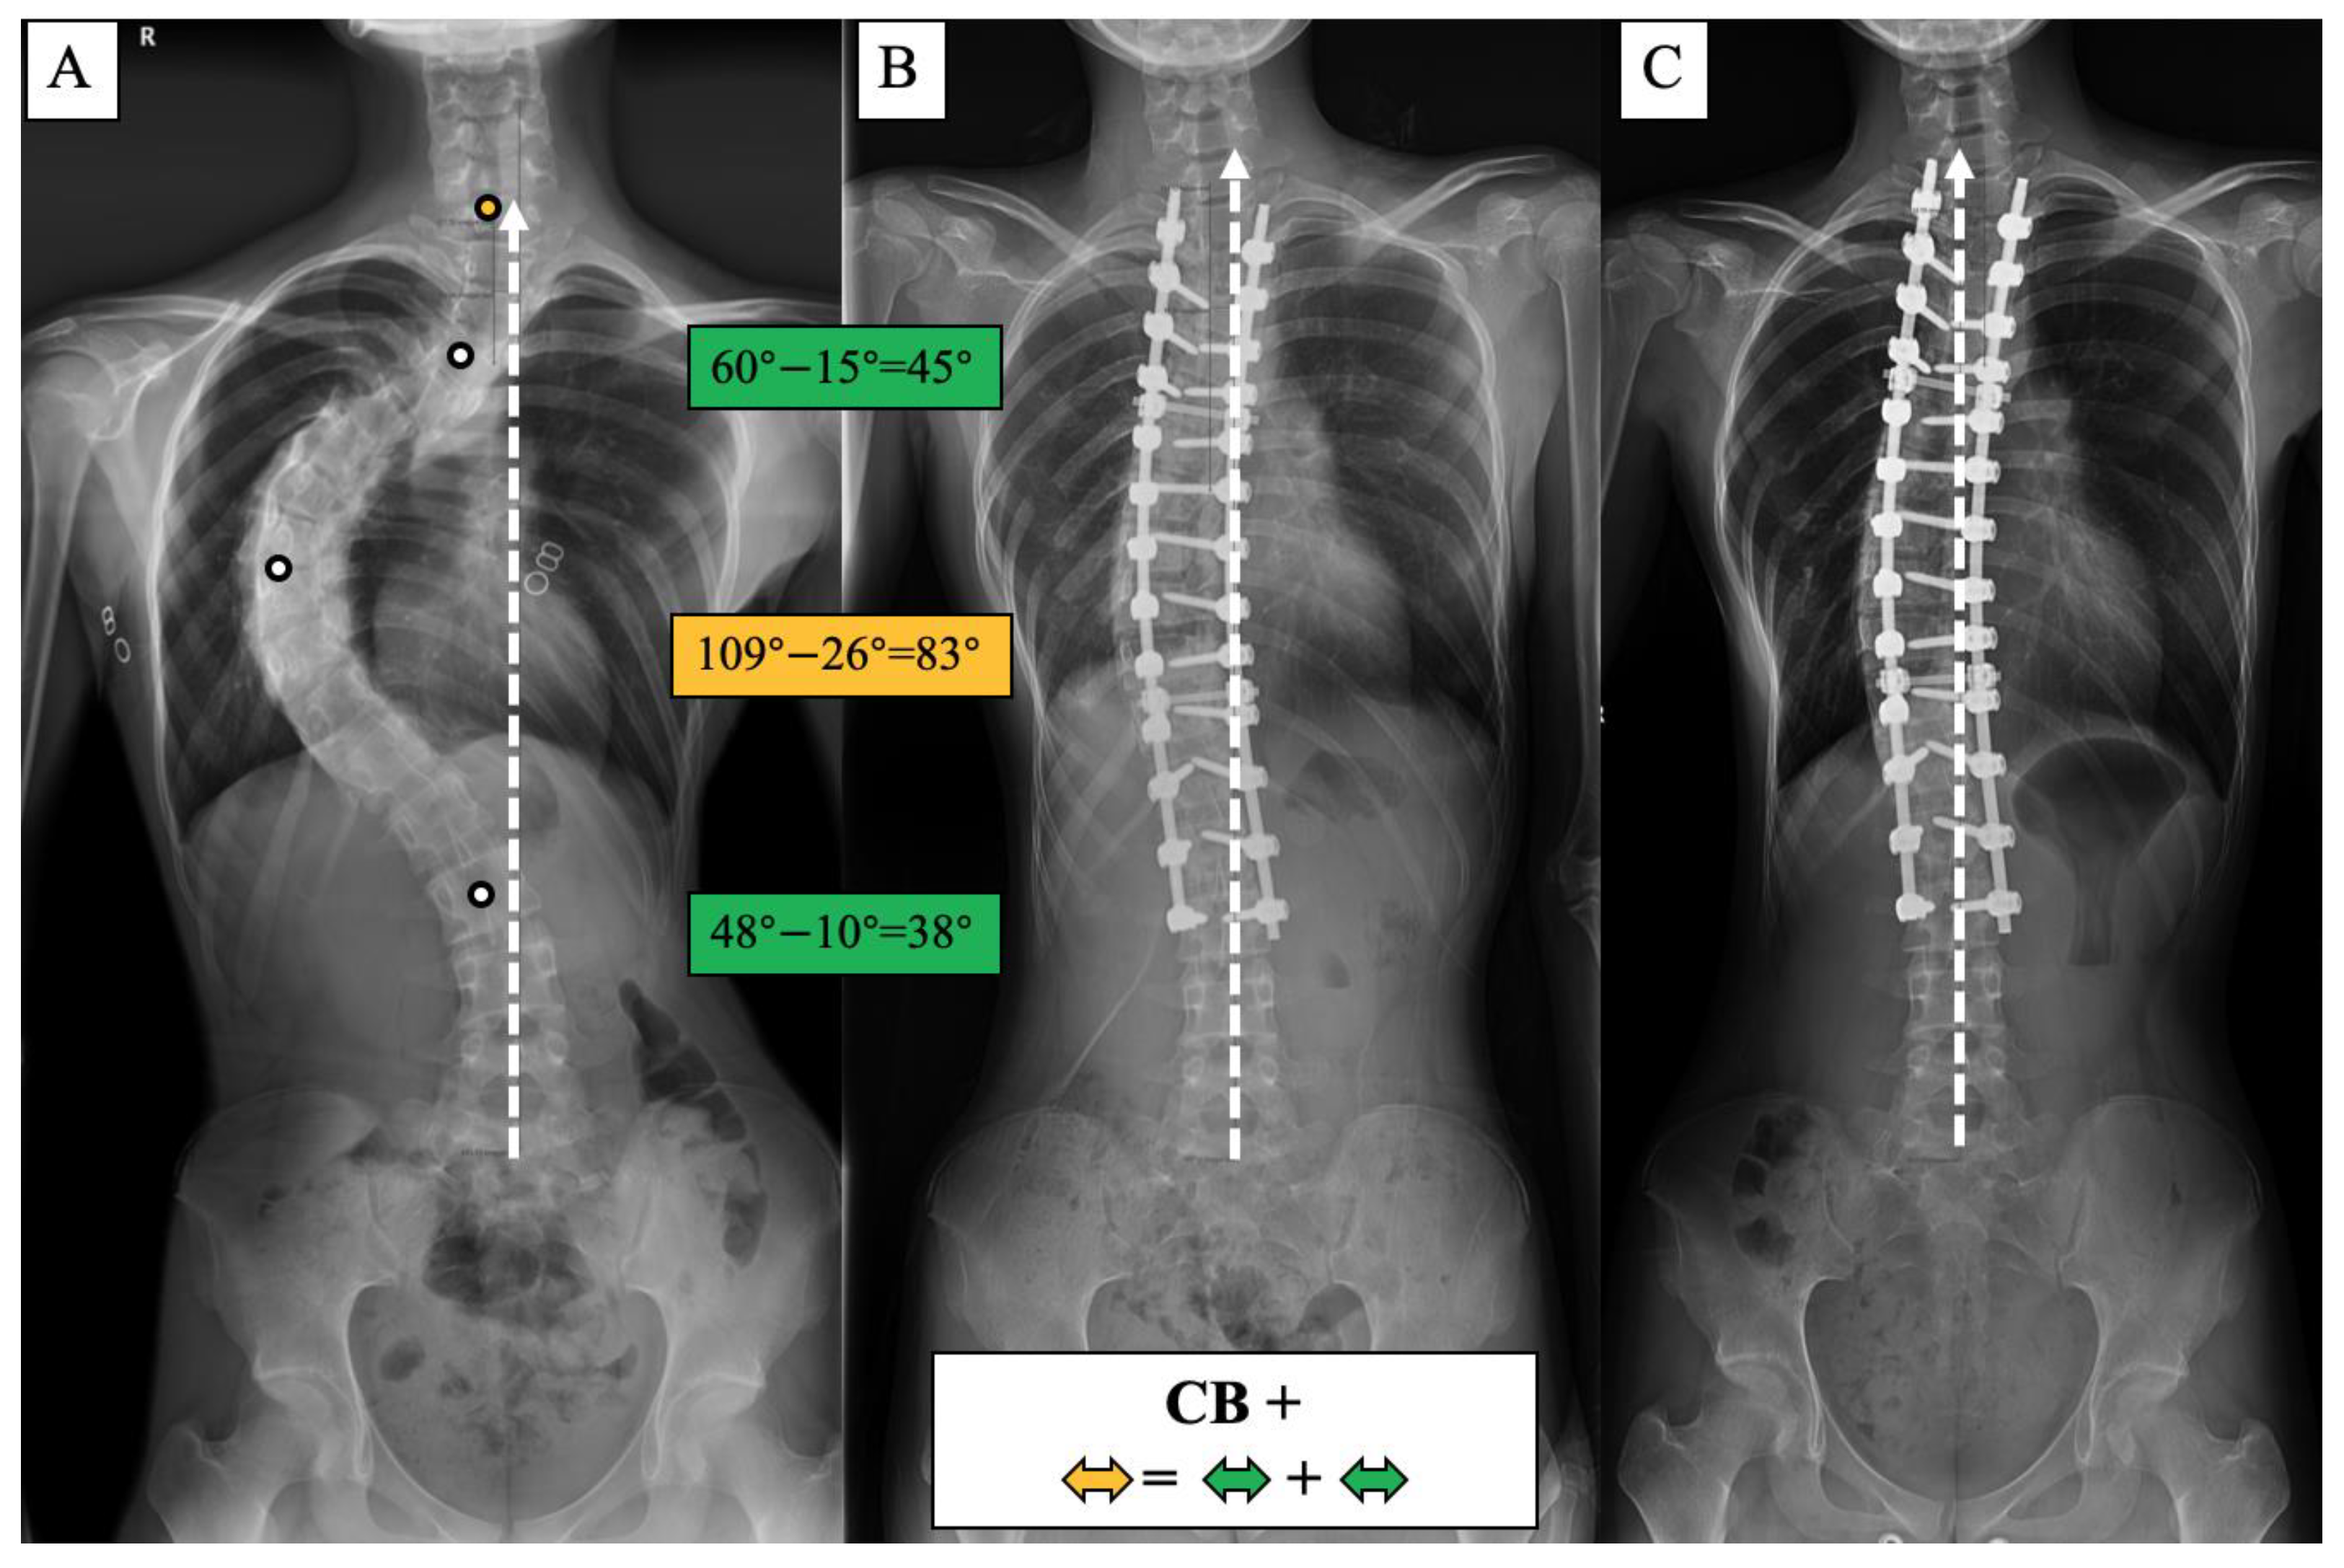

Figure 6.

CB+ case, 25-year-old female AdIS patient ((A): preoperation, (B): postoperation, and (C): 3-year follow-up). The main thoracic curve was corrected from 109° to 26° (83° correction). The upper thoracic curve was corrected from 60° to 15° (45° correction), and the thoracolumbar curve was corrected from 48° to 10° (38° correction). The correction rate of the main curve matched the compensatory curves, and the coronal plane balance was maintained after surgery and long-term follow-up.